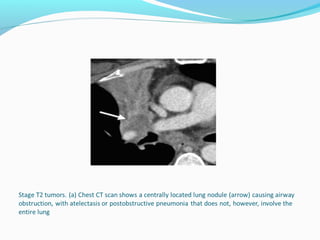

T2 - tumor Greaterthan 3 and smaller than 7 cm Invasion of the visceral pleura Atelectasis or obstructive pneumopathy involving less than the whole lung Tumor involving the main bronchus 2 cm or more distal to the carina.